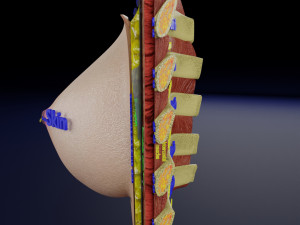

This is a 1:1 scaled model of right breast cut opened in sagittal plane to reveal its internal antomy and histology (schematic). The deeper parts and fascial layers are also depicted to give a very detailed approach to the model. The full layers starting from skin, nipple areola, till intercodtal muscles and ribs are also depicted.

breast mammary gland female chest wall anatomy human medical science reproductive genitalia muscle fascia milk nipple areola subcutaneous fatДо даного товару немає коментарів.